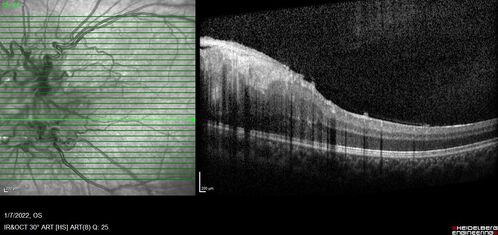

Combined hamartoma of the retina and retinal pigment epithelium

8 year old boy failed vision screening at school. VA 20/20 OD, 20/40 OS